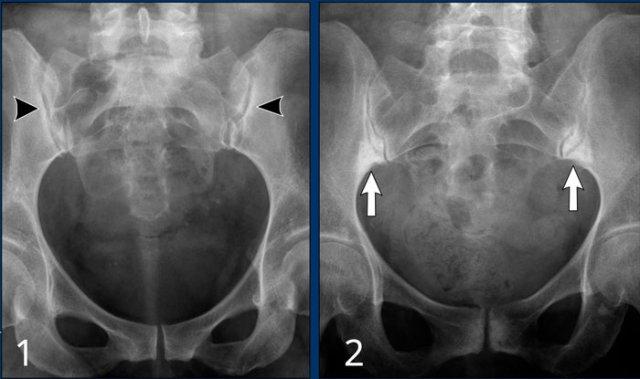

Hình ảnh X-quang khung chậu của bệnh nhân viêm khớp do lao tại khớp háng trái.

Có hẹp khe khớp kín đáo kèm theo xơ cứng dưới sụn tại khớp háng trái.

Các dấu hiệu X-quang này không đặc hiệu và rất có thể là biểu hiện của thoái hóa khớp.

Tiếp tục xem hình ảnh MRI…

Điều bất ngờ với tất cả mọi người là có nhiều ổ áp-xe.

Khi hình thành áp-xe lan rộng như vậy trong khi biểu hiện lâm sàng lại tối thiểu, cần luôn nghĩ đến viêm khớp do lao.

Chẩn đoán viêm khớp do lao được xác lập bằng chọc hút dịch khớp.

Xơ cứng dưới sụn và bào mòn hai bên khớp cùng chậu do viêm khớp cùng chậu.

MRI

MRI chuỗi xung T1W sau tiêm thuốc tương phản từ của cùng bệnh nhân cho thấy bờ khớp cùng chậu không đều do bào mòn.

Có ngấm thuốc ở xương dưới sụn và phù nề tủy xương.

Không có tràn dịch khớp.

Cuộn qua các hình ảnh MRI và so sánh với các dấu hiệu trên X-quang (hình ảnh cuối cùng).

Chẩn đoán phân biệt viêm khớp cùng chậu:

- Thoái hóa khớp: xơ cứng dưới sụn hai bên khớp cùng chậu không kèm bào mòn.

- Viêm xương đặc xương chậu (Osteitis condensans ilii): xơ cứng hình tam giác hai bên ở xương chậu tiếp giáp với khớp cùng chậu.

Chẩn đoán viêm khớp cùng chậu có thể gặp khó khăn khi chỉ dựa vào X-quang. Việc bổ sung X-quang cột sống thắt lưng hoặc các phương tiện chẩn đoán khác có thể giúp tăng độ chắc chắn trong chẩn đoán.

Viêm khớp cùng chậu giai đoạn muộn với dính khớp cùng chậu.